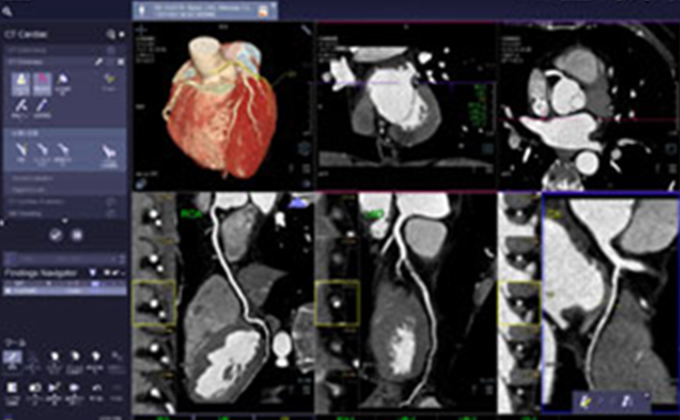

3D医用画像処理ワークステーション ziostation2

画像提供:アミン株式会社

画像診断支援システム

シーメンス社のSyngo.Viaを導入し、スムーズで的確な読影と、シームレスな画像診断環境の構築を目指しています。

画像提供:シーメンス・ジャパン株式会社